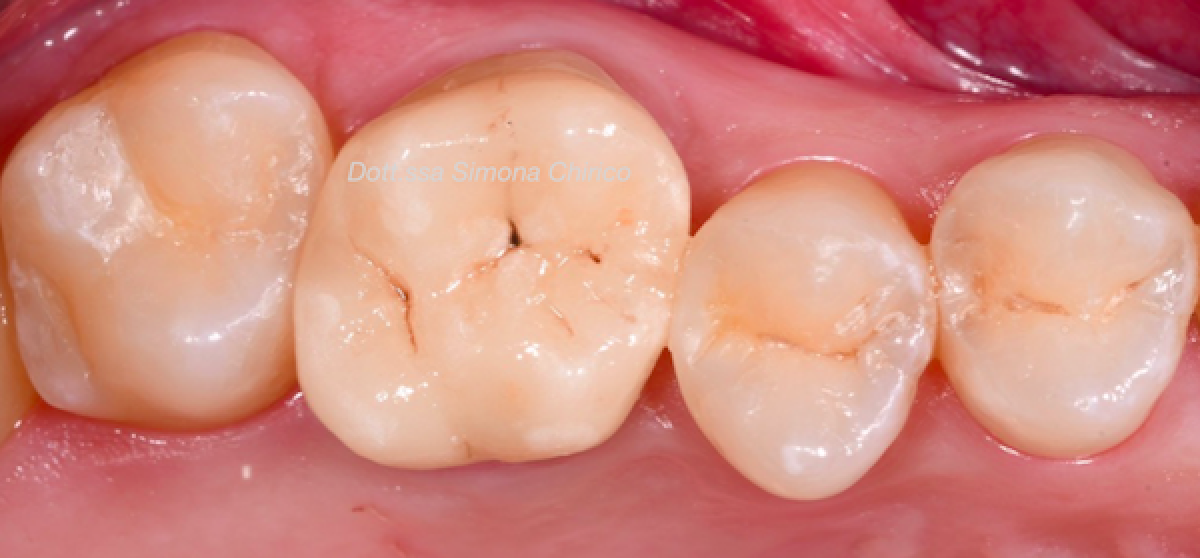

33-year-old male patient with negative medical history, who came for a visit many years after the last dental check-up. He reported pain on chewing of the first upper molar. The physical examination (fig 1) showed the presence of an old and extensive composite filling on 1.6 . The cold test performed on this tooth was negative and highlighted the presence of an irreversible pulp pathology. The percussion test was positive.